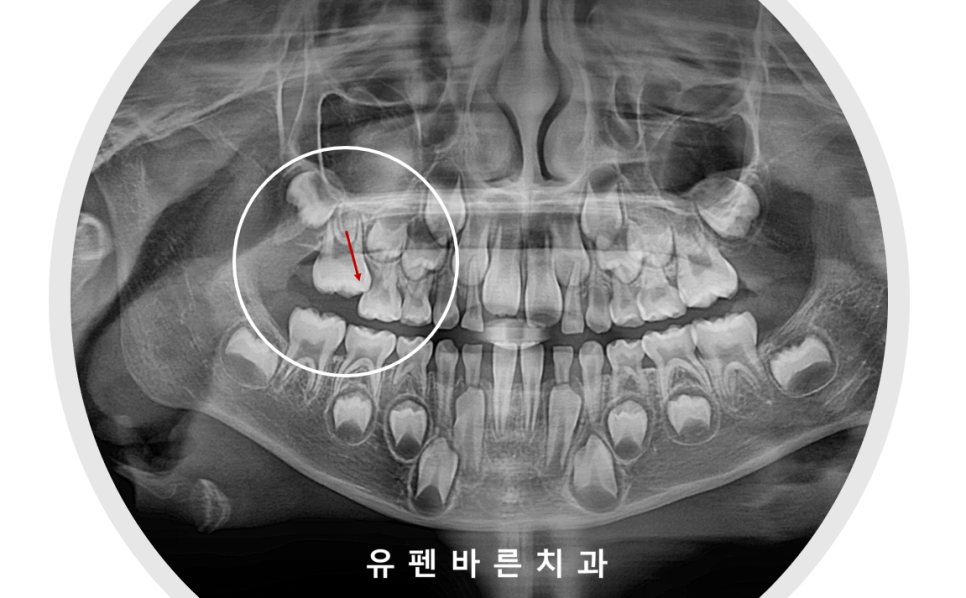

또한

이 아이의 경우

오른쪽 위의 첫번째 영구치가

앞 유치에 걸려

맹출이 잘 되지 못하고 있었는데요,

halterman 이라는 장치를 통해

어금니의 올바른 맹출을

함께 유도해 주었습니다 :)